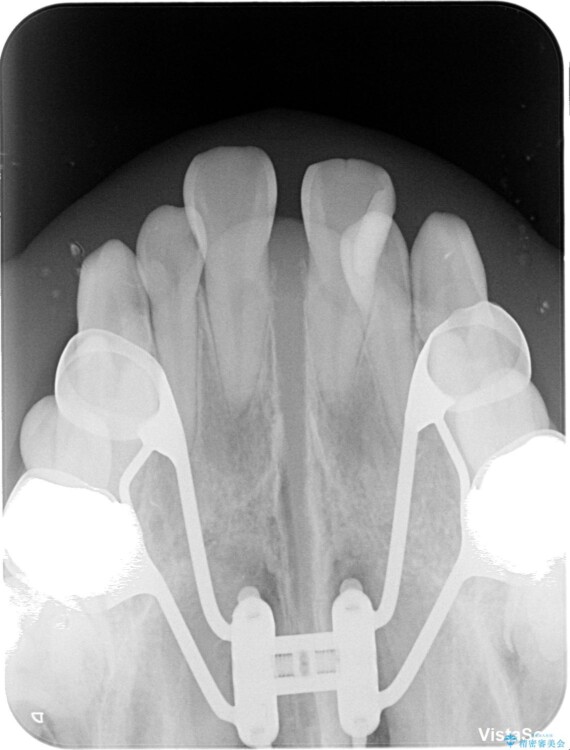

このような歯列の狭さに起因するデコボコを改善するために、**MARPE(骨に固定する上顎急速拡大装置)**を使用して、上顎の横幅を拡大し、これにより歯が並ぶためのスペースを確保し、メタルブラケットを用いて歯列を整えていく計画としました。

治療途中

• 1年でここまで変わる!歯列のがたつきと正中のズレを改善した矯正治療(メタルブラケット×MARPE) 治療途中画像